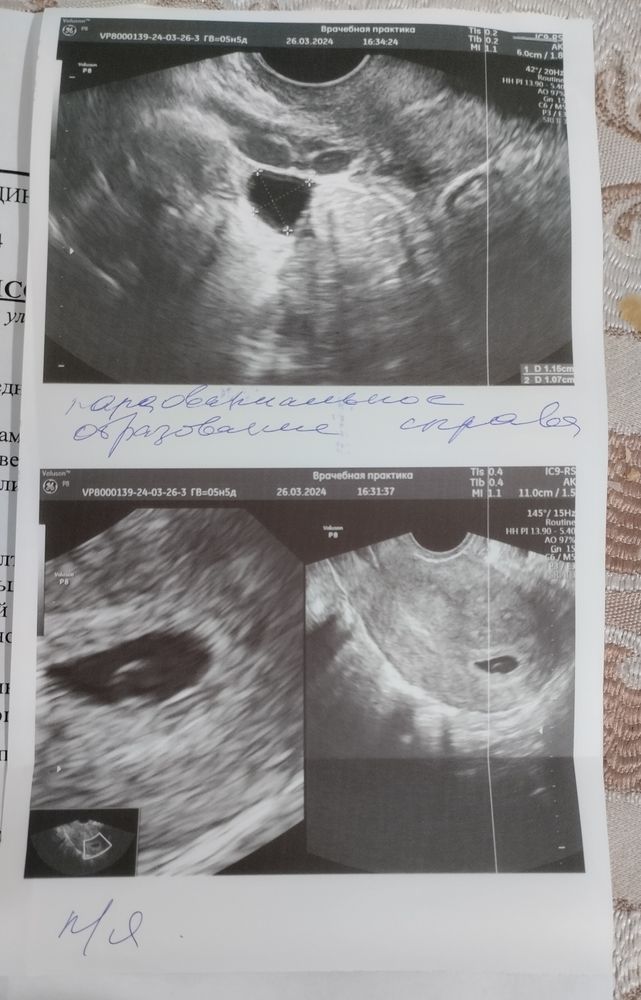

Эмбрион не растёт

Откуда будет сердце,если эмбриона ещё нет? У вас срок стоит 5,5 акушерских,для эмбриона может быть и рано даже с нормальной овуляцией,а с поздней так и подавно,ждите неделю и тогда должен появиться эмбрион и сб

Матрешка , это от первого дня месячных у вас срок сейчас 5,5 недель и пя +- примерно на этот срок, эмбриона ещё нет,так как рановато,на следующем УЗИ уже должен быть эмбрион и сб и тогда вам по УЗИ срок поставят по размеру эмбриона более точный

Матрешка , замершая это когда есть эмбрион и сб нет и в динамике не растет,а у вас эмбриона нет,откуда будет сб? Естественно не будет,нет акушерских срок у вас сейчас 5,5 недель,его считают от 1 дня месячных, эмбрион и сб смотрят ближе к 7 недели,т.е через неделю у вас будет 6,5 акушерских недель и тогда должен быть эмбрион и сб

судя по заключению у вас пустое плодное яйцо - почитайте что такое

Повторное узи надо через неделю

Я думаю, всё у Вас хорошо. У меня на вашем сроке было плодное яйцо 10 мм и желточный мешочек 3 мм. Через 12 дней видно было и эмбрион и сердцебиение.